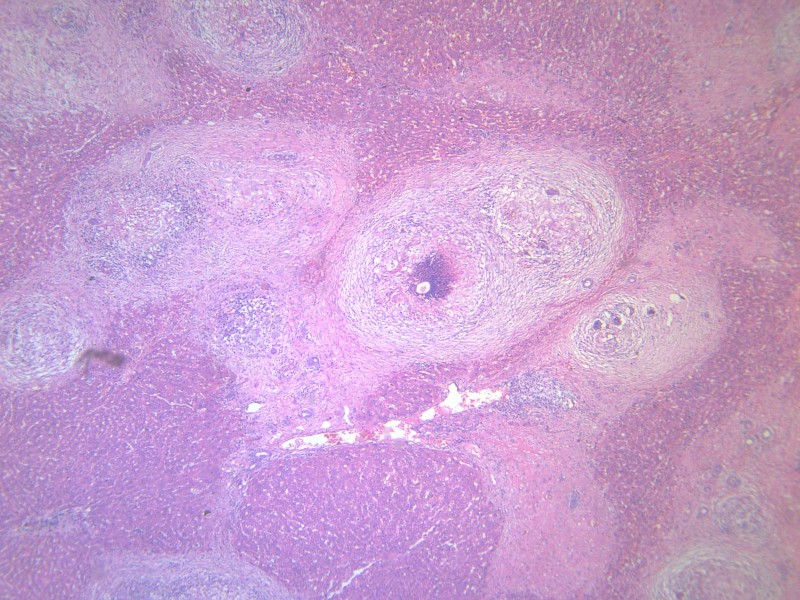

科普:肉瘤是一种“小众”肿瘤,发病率仅占所有恶性肿瘤的1%,子宫平滑肌肉瘤是子宫恶性间叶性肿瘤,占所有恶性间叶性肿瘤的25%,占所有子宫恶性肿瘤的1%,属高度恶性肿瘤,呈浸润性生长,易复发和转移,肺和肝是常见的转移部位,淋巴结和卵巢转移不常见。

2015年8月,她因一场小病“月经量明显增多”前往当地医院和天津某大医院做了子宫全切术,然而,接下来的病理结果让她和老伴儿大吃一惊:子宫平滑肌肉瘤,侵及全层子宫。

2018年11月,停化疗2年9个月,再次出现不规则阴道流血,原来治疗的北京某院检查告知复发:梭形细胞恶性肿瘤伴坏死,考虑为平滑肌肉瘤;随后分别做了3周期顺铂+表柔比星方案化疗。可是,噩梦并未结束。2019年6月份,医院复查显示:盆腔软组织肿块,约8.7cm*8.9cm*11.0cm,在医院的多学科会诊后,医生给出的答案是“没办法治了”。

图片:患者肿瘤术前(左)和术后(右)对比